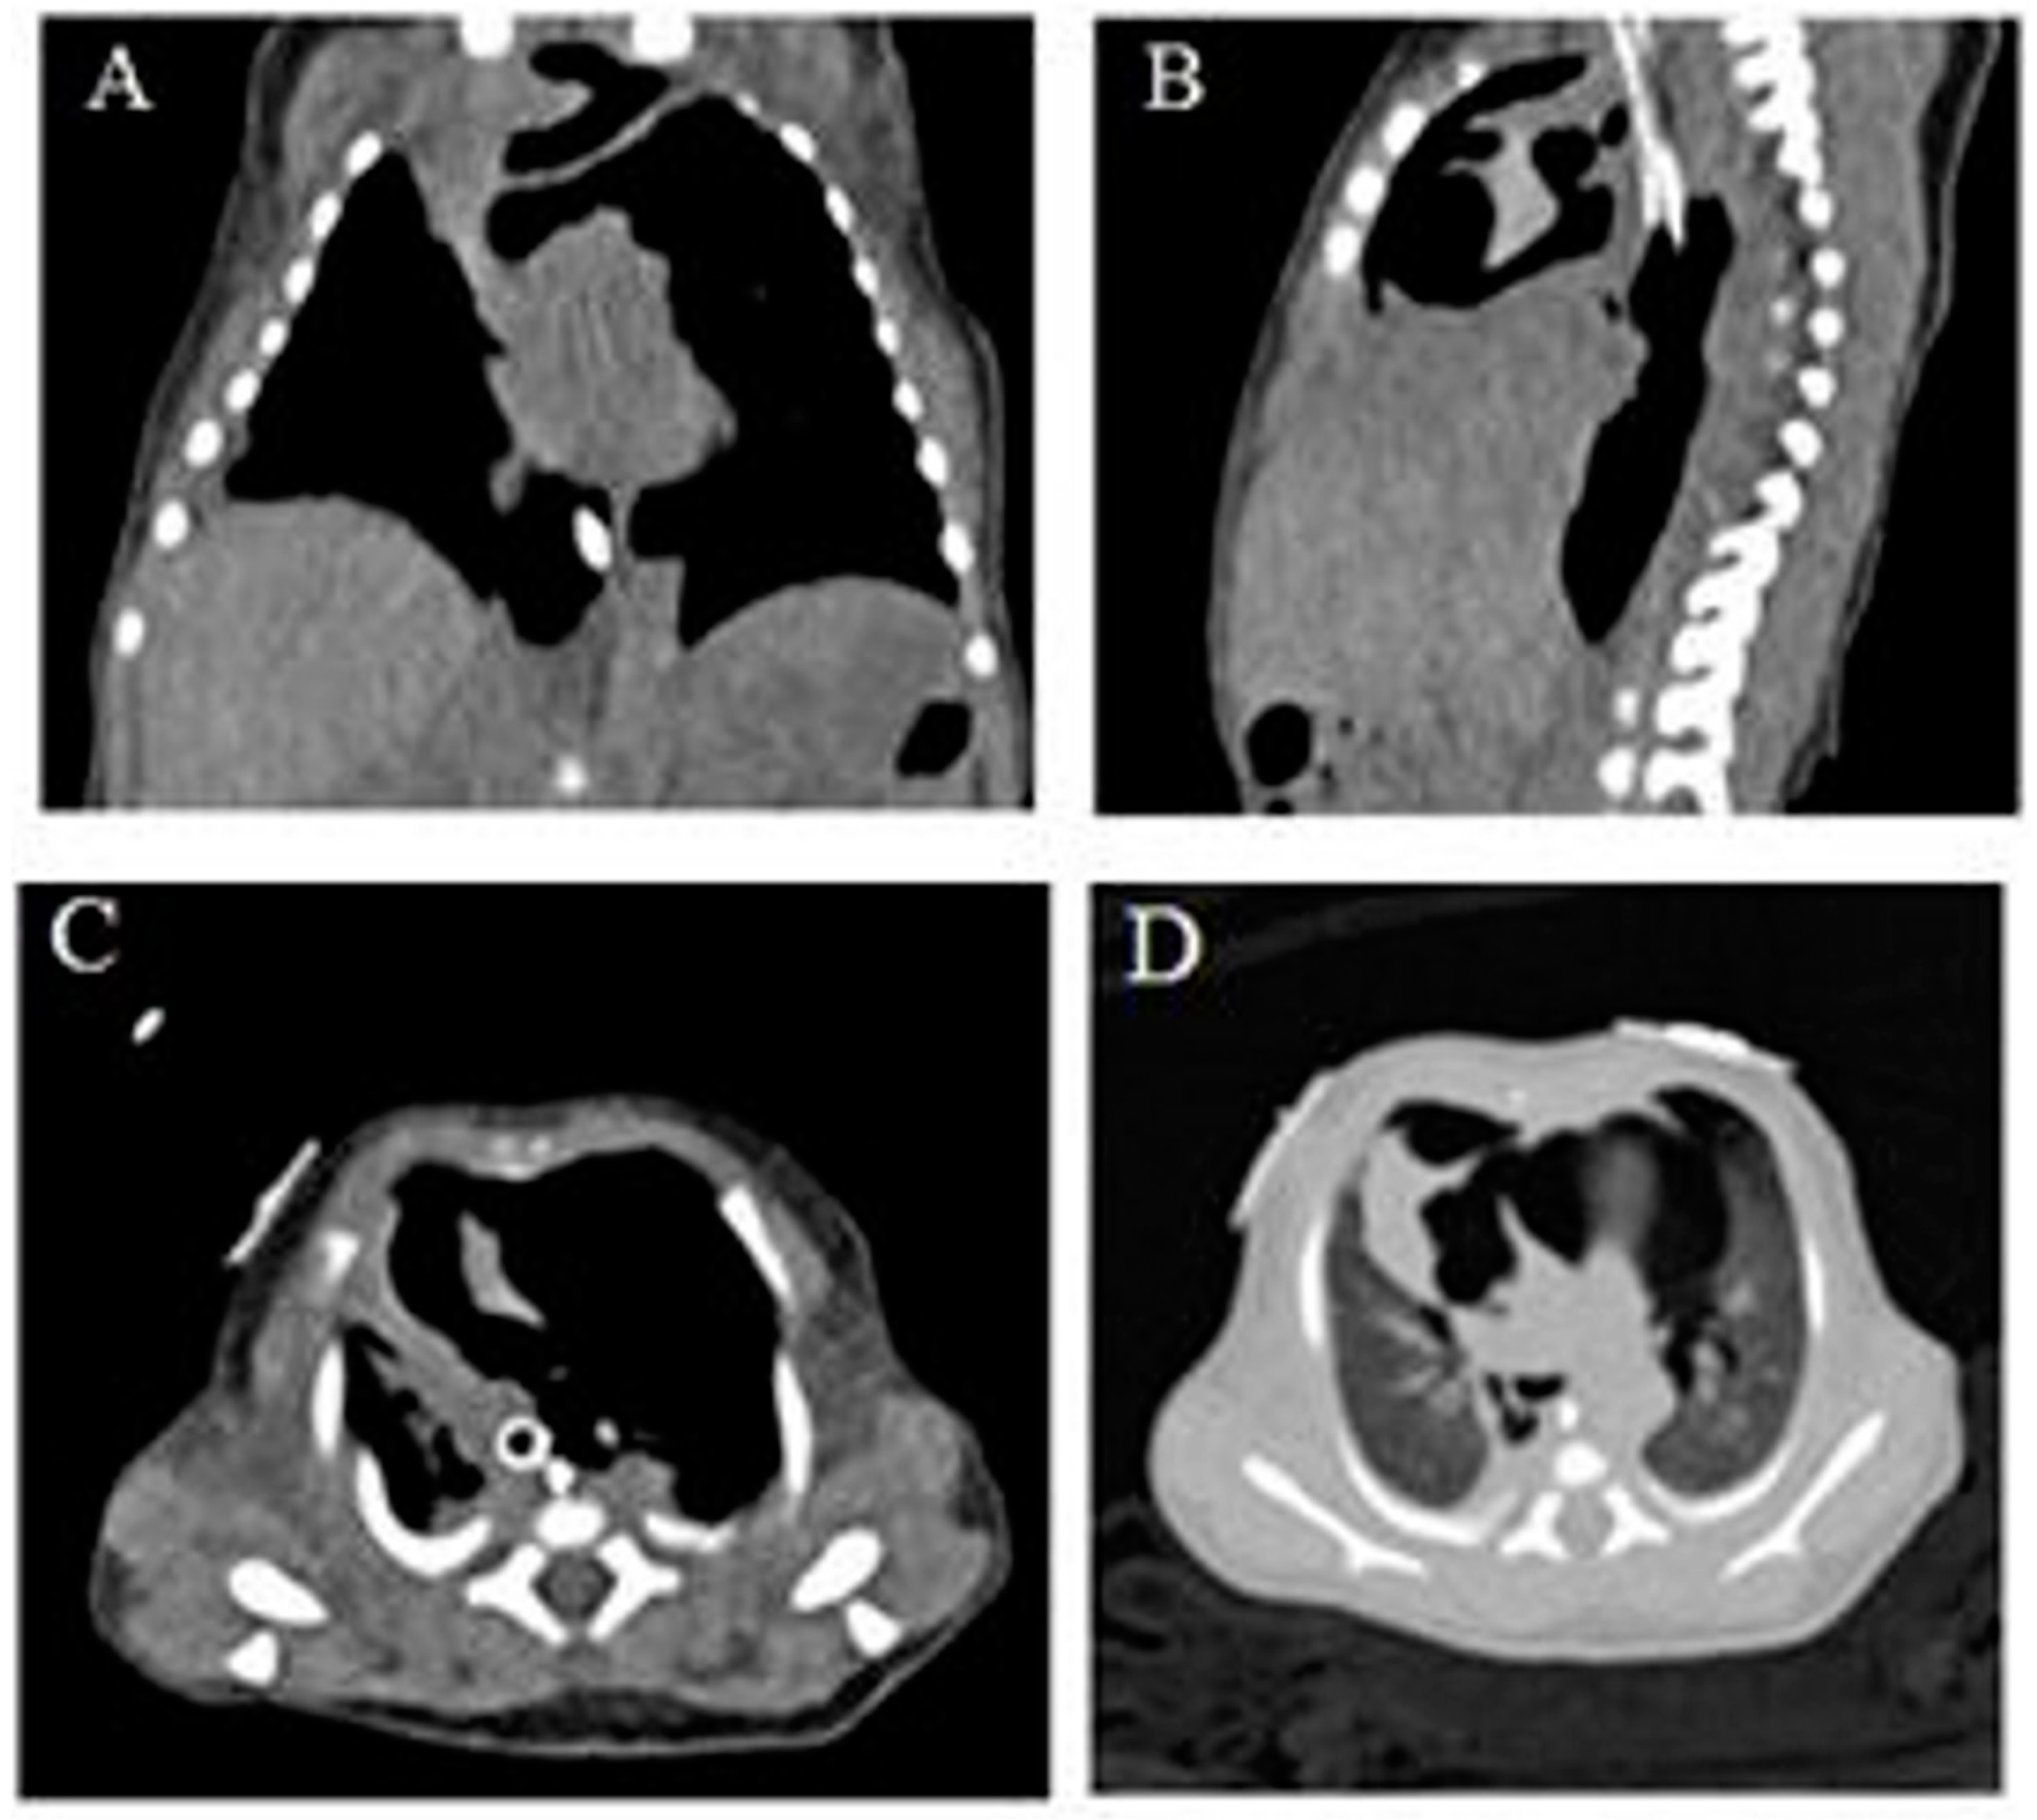

Pneumomediastinum Mimicking Congenital Pulmonary Airway Malformation

2. Case Summary